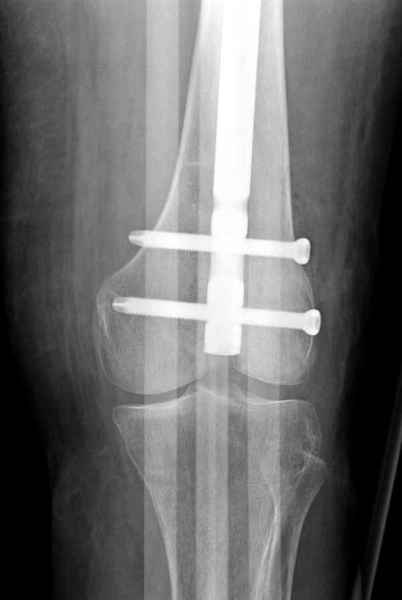

Для предупреждения кровотечения во время рассверливания, за день до операции провели эмболизацию сосудов питающий метастаз. http://radiology.rsnajnls.org/cgi/reprint/150/3/673.pdf (7-11, 12-15-16)

С минимальным рассверливанием и ретроградным методом провели остеосинтез бедра 12 мм гвоздем. (17-20)

Кровопотеря во время операции меньше 100 мл.